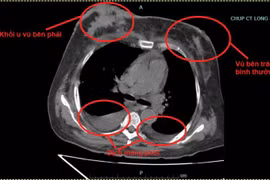

(khoahocdoisong.vn) - Mới đây, Bệnh viện T.Ư Quân đội 108 tiếp nhận một nữ bệnh nhân được chẩn đoán ung thư biểu mô tuyến thùy trên phổi phải di căn xương, đã điều trị hóa chất đáp ứng tốt nhưng vì nghe theo mách bảo trên mạng, dùng bài tập khí công có nguốn gốc nước ngoài kết hợp ăn kiêng để trị bệnh, khi quay lại bệnh viện điều trị tiếp thì sức khỏe đã yếu đi rõ rệt.